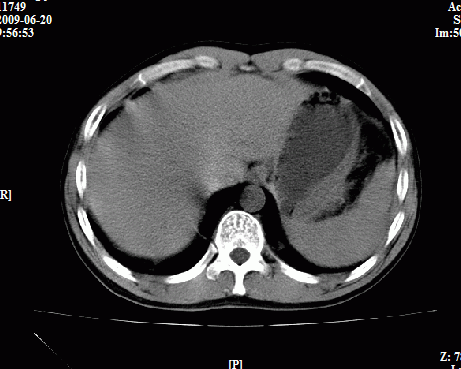

以下是引用随光逐影在2009-6-23 11:37:00的发言:[br]1)考虑胃癌;建议行胃镜检查进一步明确诊断。2)肝右叶肝内胆管结石(或钙化)。

以下是引用zxl51642在2009-6-23 11:31:00的发言:[br]胃大弯侧壁明显增厚呈软组织肿块,考虑胃癌可能性大,建议胃镜活检。